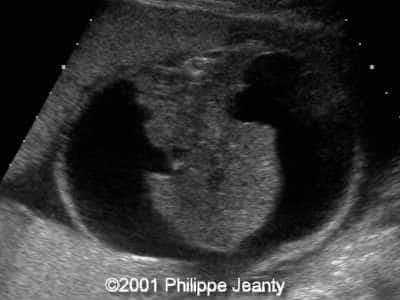

This 2nd trimester fetus has the following images (actually, these images remained unchanged for several weeks)

• very enlarged lungs on both sides

• inversion of the diaphragm that is convex towards the abdomen

• small compressed heart

• ascites but no generalized hydrops (no skin thickening for instance)

A much more common diagnosis for a bilateral echogenic lung associated with microcardia and ascites (Budd-Chiari phenomenon) is Larynx, atresia or as reported by several the CHAOS syndrome which stands for Congenital High Airway Obstruction Syndrome (which is typically laryngeal or tracheal atresia). This is the diagnosis that was indeed suspected in this fetus.